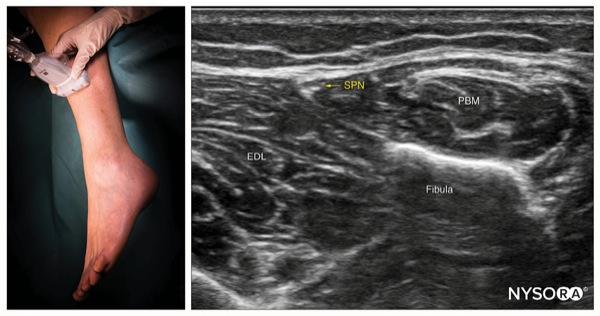

To Block the Superficial Peroneal Nerve

Place the transducer in a transverse orientation over the lateral aspect of the distal leg, 5 to 10 cm proximal to the lateral malleolus, over the fibula (Figure 5).

Identify the superficial peroneal nerve as a hypoechoic flat structure at the intersection between the crural fascia and intermuscular septum separating the lateral and anterior muscular compartments.

Insert the needle using an in-plane or out-of-plane approach into the fascial plane containing the nerve (Figure 6).

Inject 1 to 2 mL of local anesthetic to confirm proper needle positioning by observing the spread surrounding the nerve within the fascial plane.

Complete the block with a volume of 3 to 5 mL.